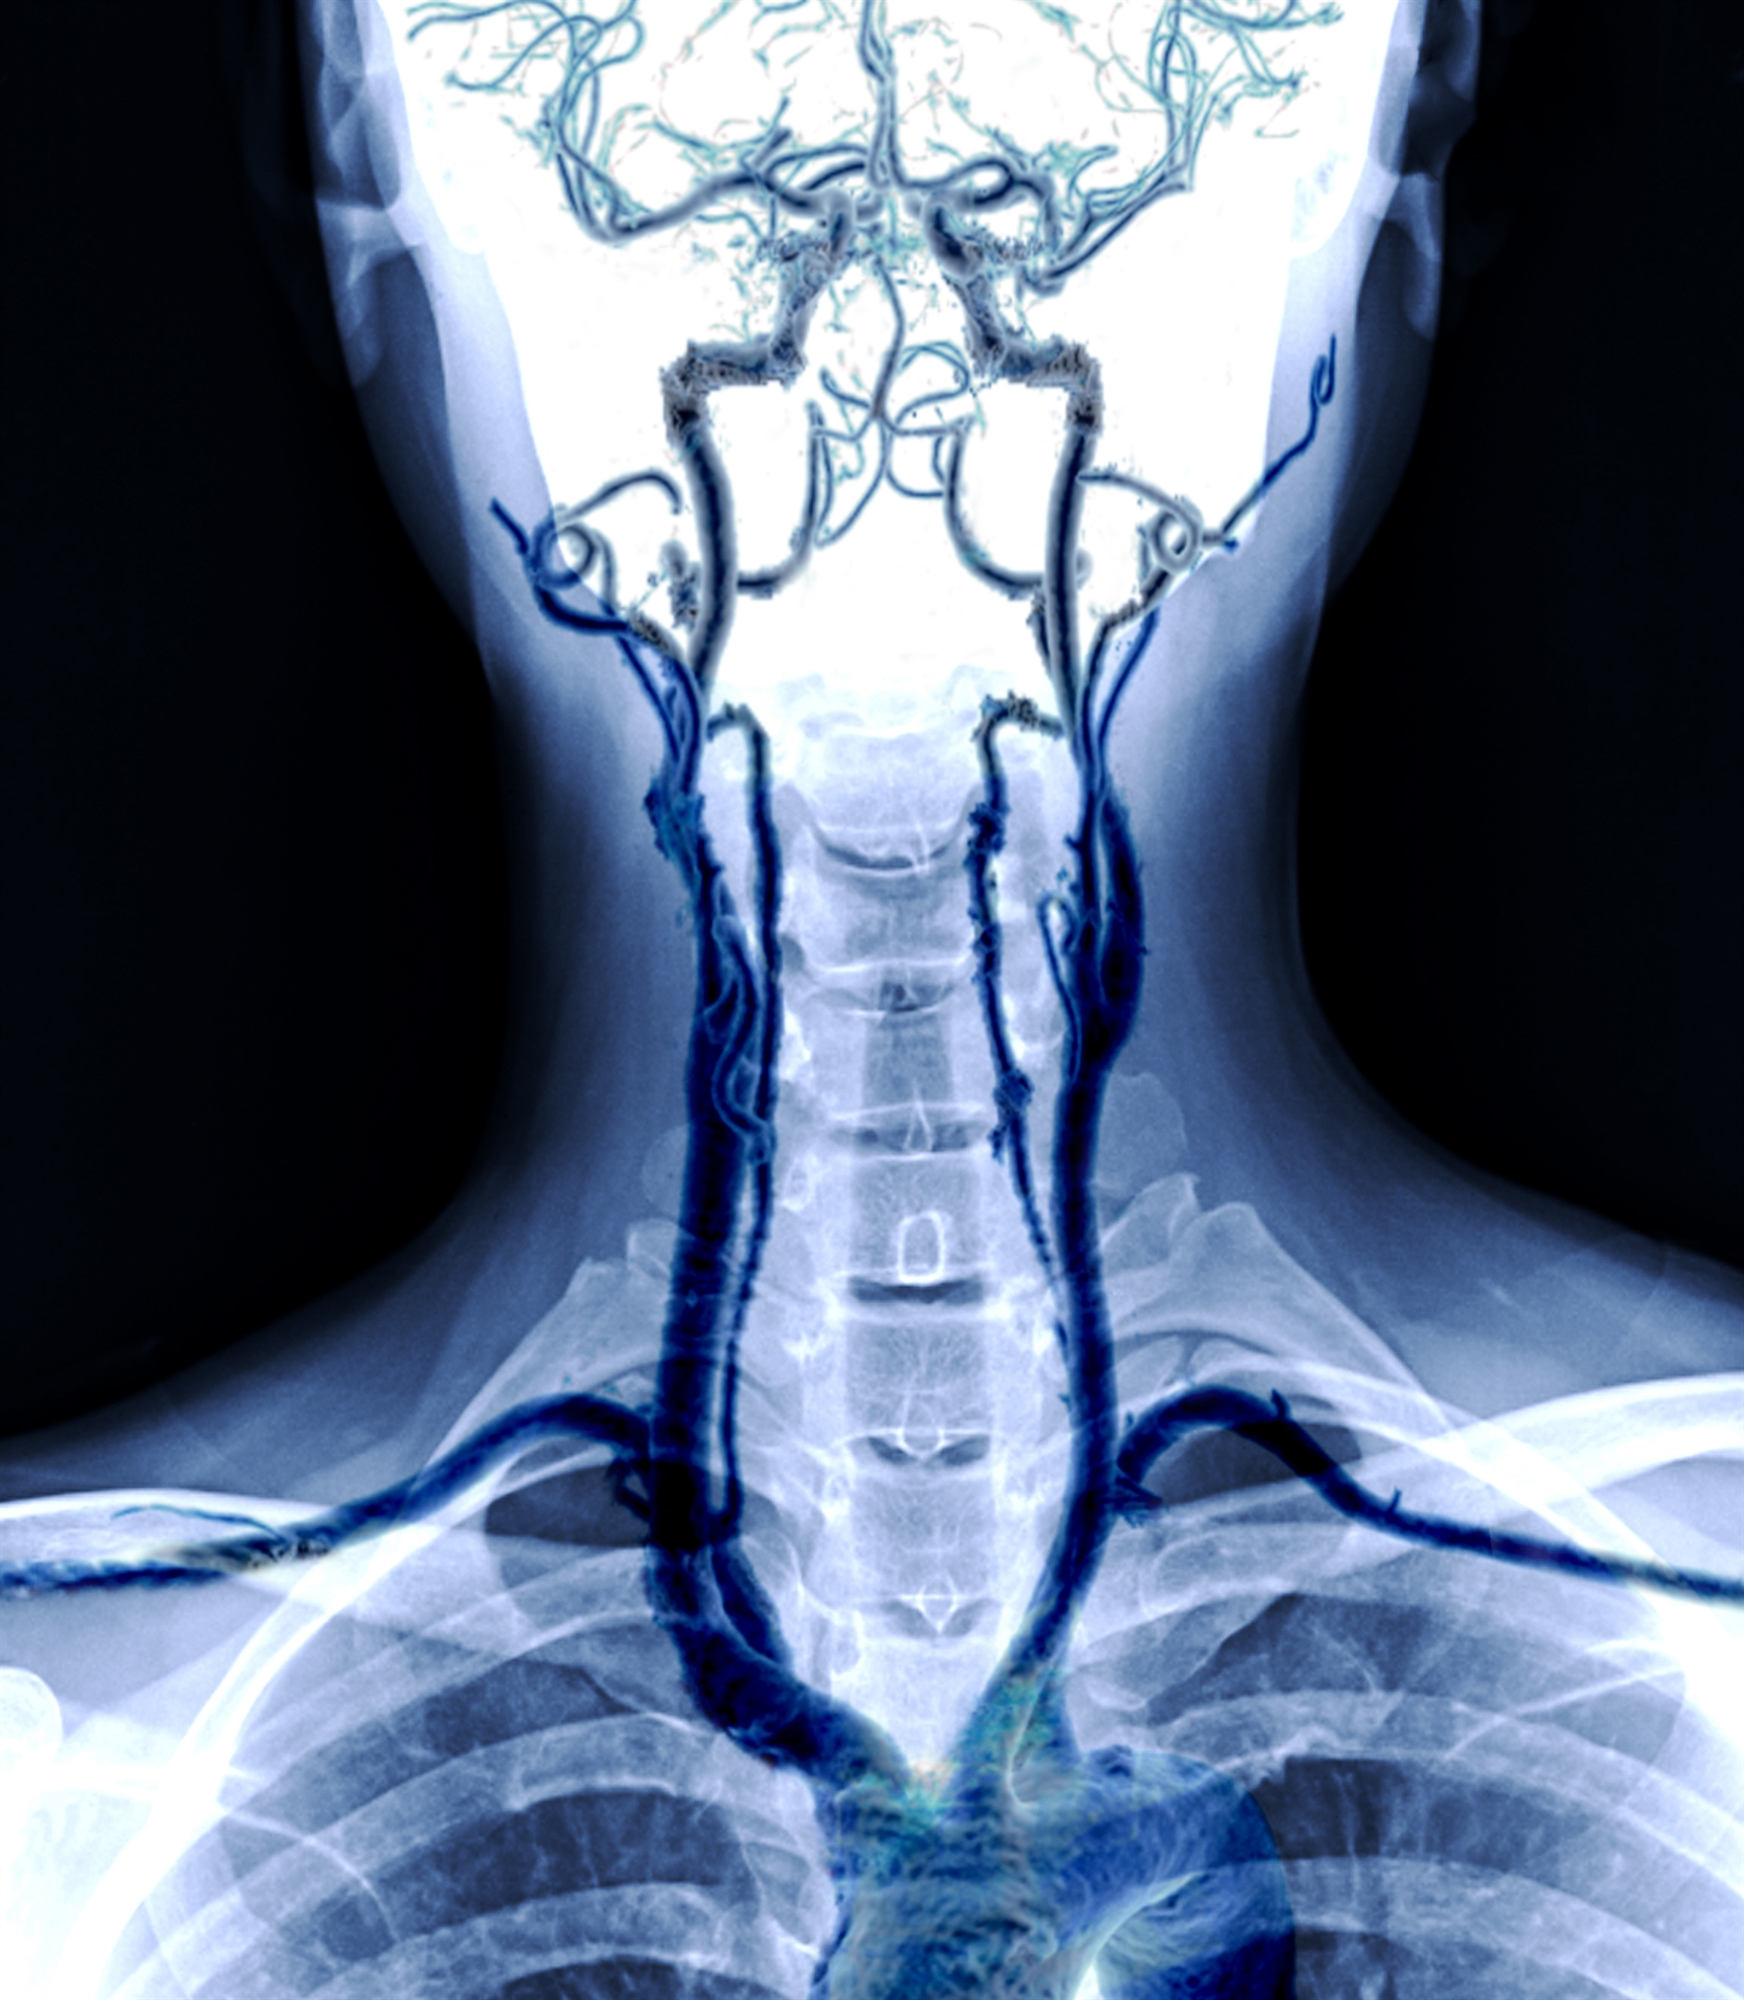

Έχετε μήπως λάβει ποτέ στο ηλεκτρονικό σας ταχυδρομείο ένα φυλλάδιο που διαφημίζει μια «απλή, ανώδυνη υπερηχογραφική εξέταση» η οποία μπορεί να εντοπίσει την επικίνδυνη ανάπτυξη αθηρωματικής πλάκας; Όταν προσφέρονται από εμπορικές εταιρείες, οι εξετάσεις αυτές γίνονται στις ΗΠΑ συνήθως σε εκκλησίες, κέντρα αναψυχής ή βανάκια. Πραγματοποιούνται όμως επίσης σε πιστοποιημένα ιατρικά κέντρα. Μία από αυτές τις εξετάσεις ελέγχει τις καρωτίδες, δηλαδή τις αρτηρίες που διατρέχουν τις δύο πλευρές του λαιμού και τροφοδοτούν τον εγκέφαλο με αίμα.

Όπως και οι αρτηρίες που τροφοδοτούν με αίμα την καρδιά και άλλα μέρη του σώματος, οι καρωτίδες μπορεί να φράξουν από εναποθέσεις λιπών (αθηρωματική πλάκα), οι οποίες στενεύουν τον αυλό των αρτηριών και παρεμποδίζουν τη ροή του αίματος. Ωστόσο, αντίθετα από αυτό που μπορεί να νομίζετε, ο έλεγχος για αυτό το πρόβλημα –που ονομάζεται στένωση καρωτίδων– σπανίως έχει νόημα, ιδίως με χρήση μιας προληπτικής εξέτασης η οποία πραγματοποιείται από μια κερδοσκοπική εταιρεία.

Όταν οι άνθρωποι φτάνουν σε ηλικία 75-80 ετών, δεν είναι σπάνιο να εμφανίσουν οι καρωτίδες τους ενδείξεις πάχυνσης. Ωστόσο, περίπου μόνο ένα στα 100 άτομα στον γενικό πληθυσμό έχει σημαντική στένωση των καρωτίδων. Η στένωση των καρωτίδων συνήθως δεν προκαλεί κάποια βλάβη, εκτός και αν η στένωση είναι ιδιαίτερα σοβαρή – απόφραξη κατά 70% ή μεγαλύτερη. Υπάρχει κίνδυνος να συμβεί ρήξη της πλάκας και να σχηματιστεί θρόμβος που εμποδίζει την παροχή αίματος σε τμήμα του εγκεφάλου, μια επείγουσα κατάσταση που είναι γνωστή ως ισχαιμικό αγγειακό εγκεφαλικό επεισόδιο. Ωστόσο, η στένωση των καρωτίδων ευθύνεται μόνο για περίπου ένα στα 10 ισχαιμικά αγγειακά εγκεφαλικά επεισόδια, σύμφωνα με μια πανεθνική βάση δεδομένων στις ΗΠΑ.